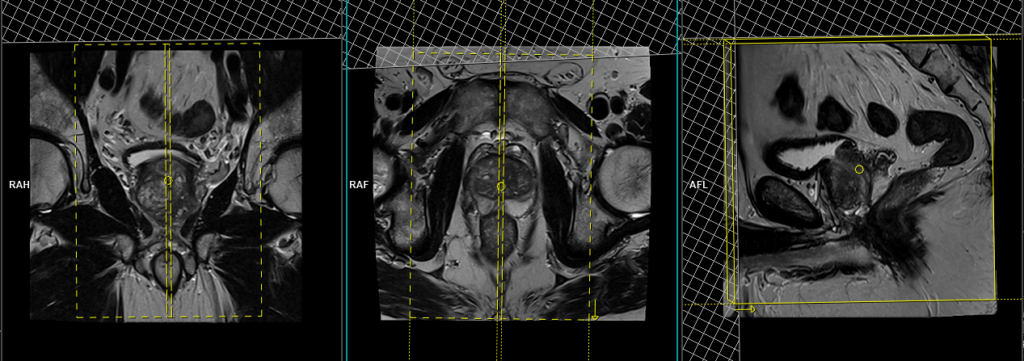

T2 tse coronal 3mm SFOV

Plan the coronal slices on the sagittal plane and angle the positioning block vertically across the prostate, as shown in the picture. Check the positioning block in the other two planes, ensuring an appropriate angle is given in the axial plane (parallel to the right and left hip joints or ischial tuberosity). The slices must be sufficient to cover the entire prostate and seminal vesicles. Additionally, to minimize artifacts stemming from arterial pulsation and breathing, consider incorporating saturation bands on the top and front of the coronal block.

Parameters

TR 3000-4000 | TE 100-120 | SLICE 3 MM | FLIP 130-150 | PHASE R>L | MATRIX 320X256 | FOV 180-230 | GAP 10% | NEX(AVRAGE) 5 |